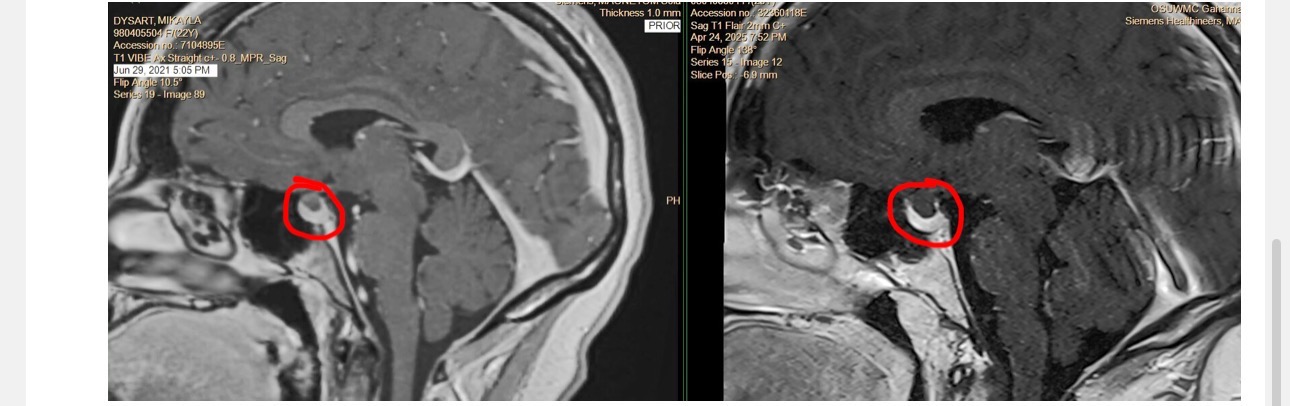

I was unexpectedly part of a mass layoff on May 19th, and shortly after, I received a life-changing diagnosis of scleroderma, a rare autoimmune condition. Now, I’m preparing to undergo brain surgery on July 17th at The James in Columbus.